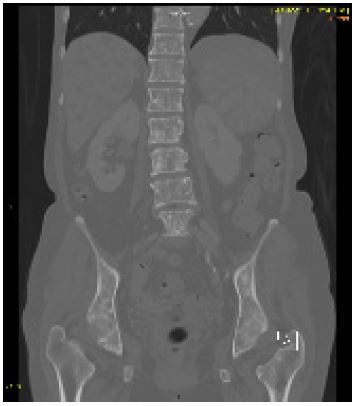

Computer tomography of the abdomen showed multiple low-density lesions of the liver, some with soft tissue attenuation but without enhancement, and borderline splenomegaly was also noted with mottled splenic enhancement. Multiple sclerotic bone lesions were noted (Figure 1).

On a CT scan, the spleen demonstrated borderline enlargement, measuring 12 cm and contained multiple hypodense lesions. There were also innumerable liver lesions, some of which contained non-enhancing foci of internal hyperdensity. Extensive tiny sclerotic metastases were noted in the axial and appendicular skeleton.

Figure 2: Coronal CT image showing extensive sclerotic bone metastases.